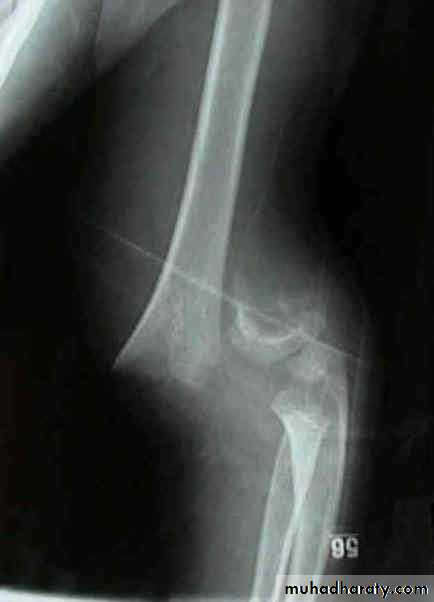

Upper limb

Fall on out stretched hand

40 years male fall on out streched hand

Radial nerve palsy after reduction